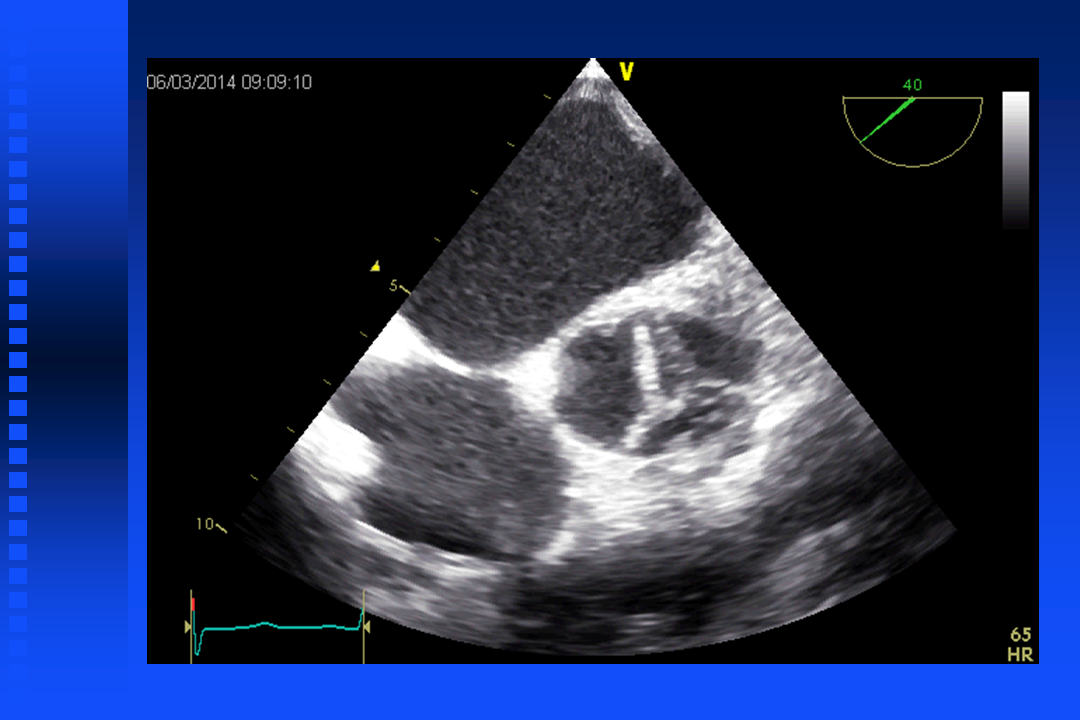

Short film Bicuspid Valve

Short film aortic valve with regurgitation

Short film mitral relaps

Short film mitral relaps with color doppler